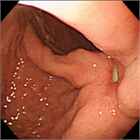

1. 難渋例の症例について画像を用いて解説した。